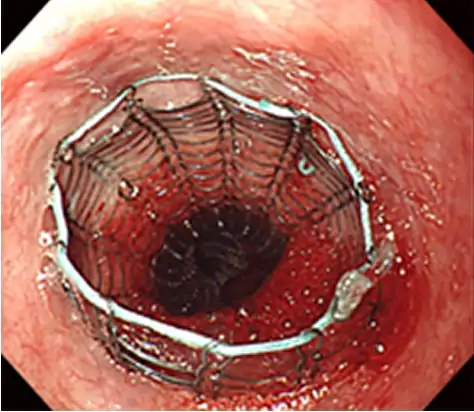

消化管ステント留置術

癌によって狭くなった消化管に金属製の「拡がるバネ」を入れ、食べ物の通りを出来る限り良くします。癌を根治させることは出来ませんが、進行癌の患者さんに、食べる喜び、便通を取り戻して頂く処置です。